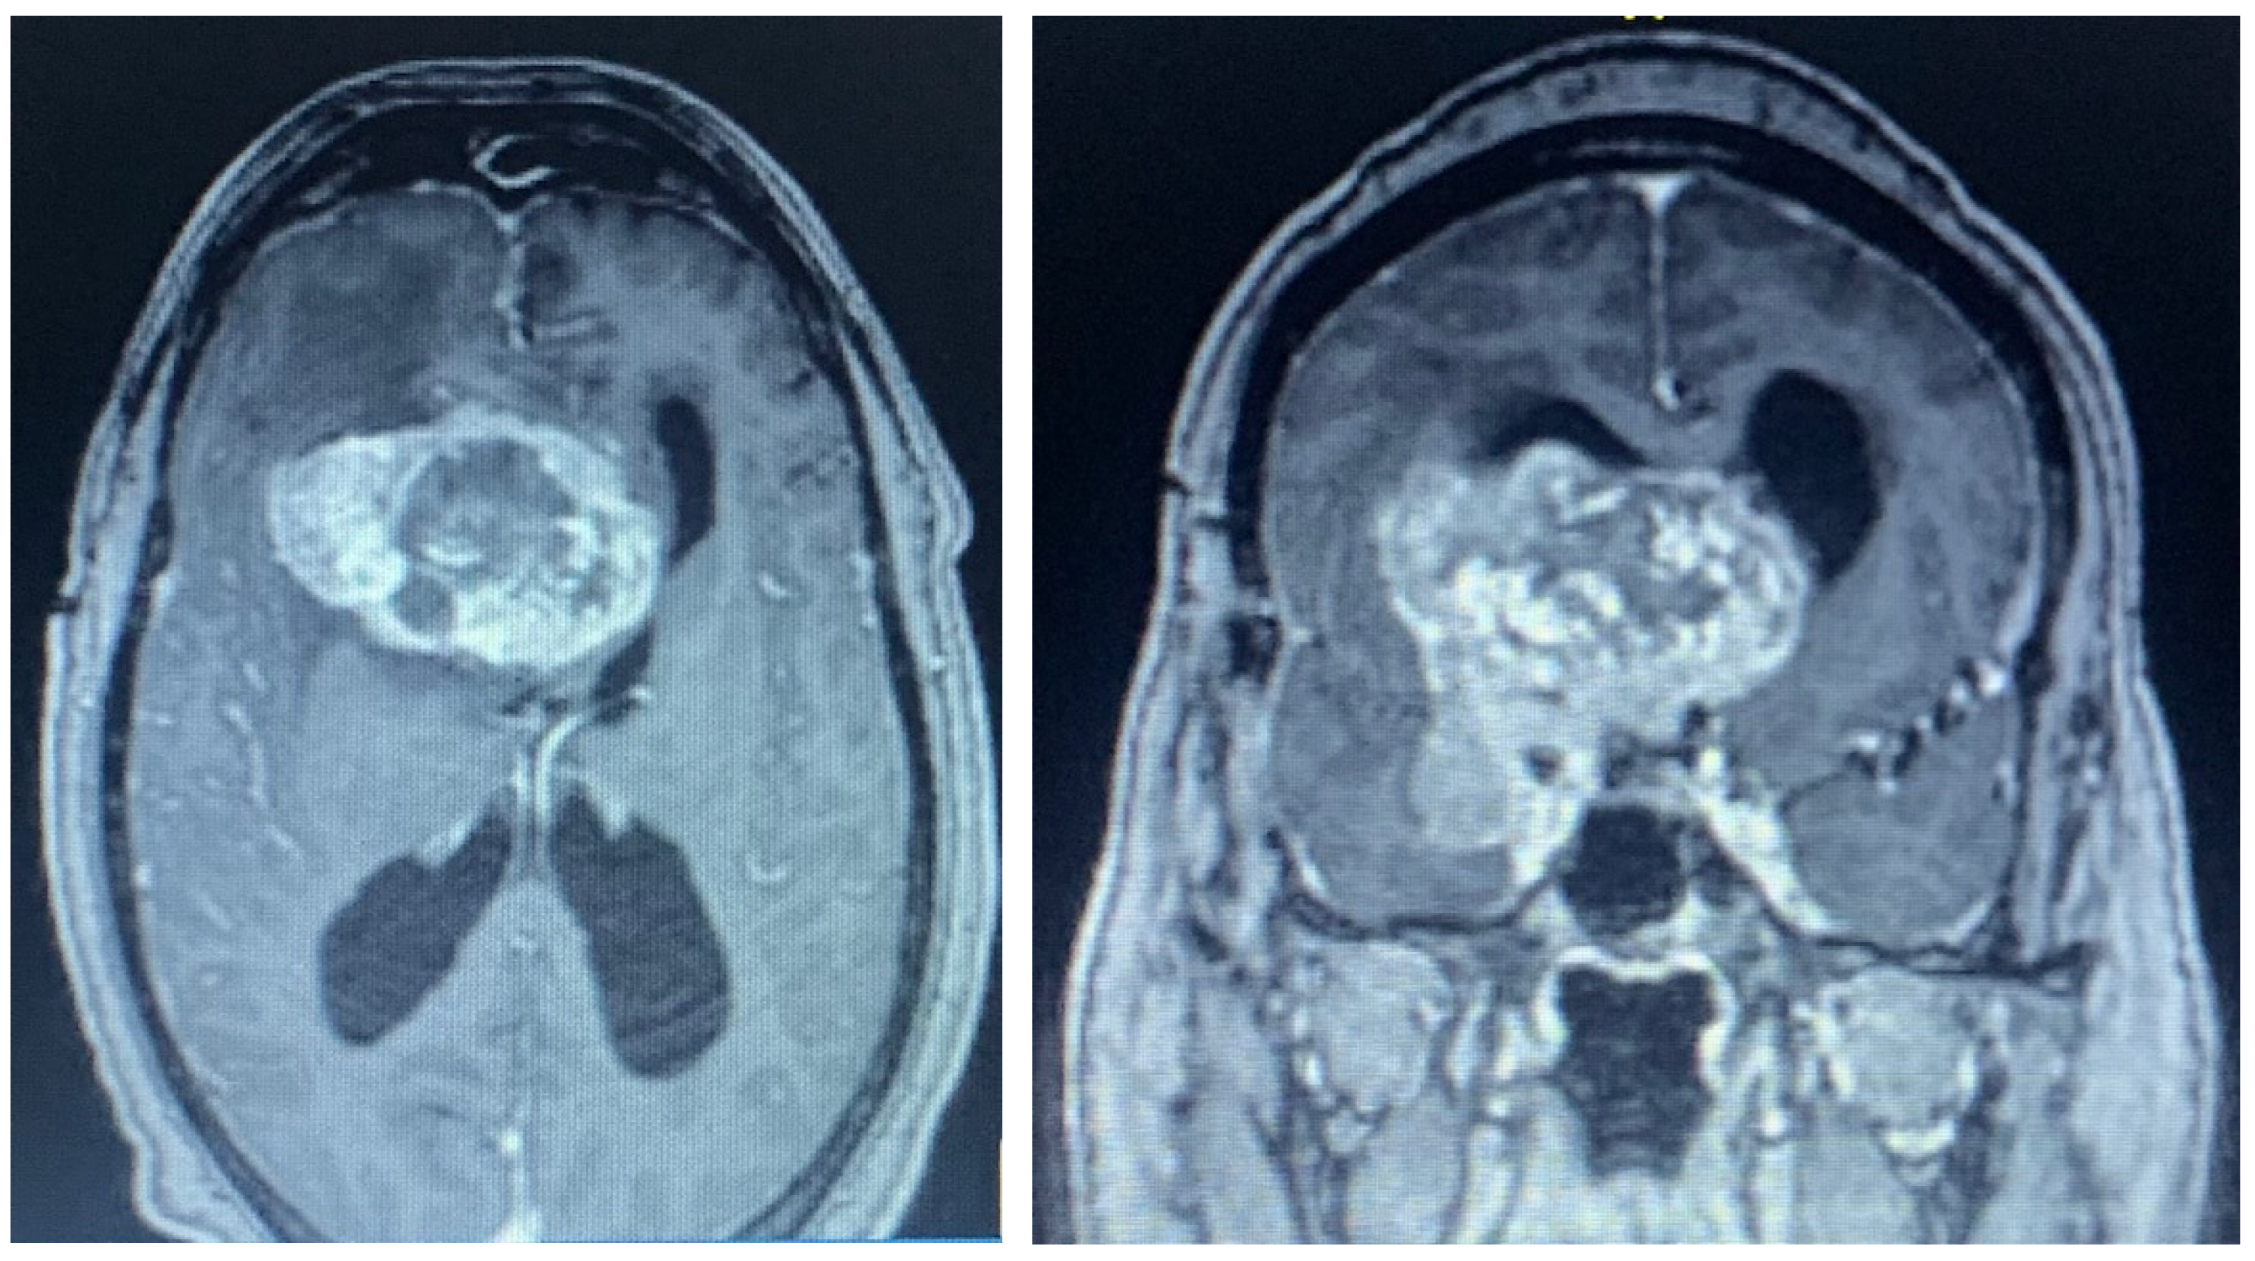

2.1. Case 1